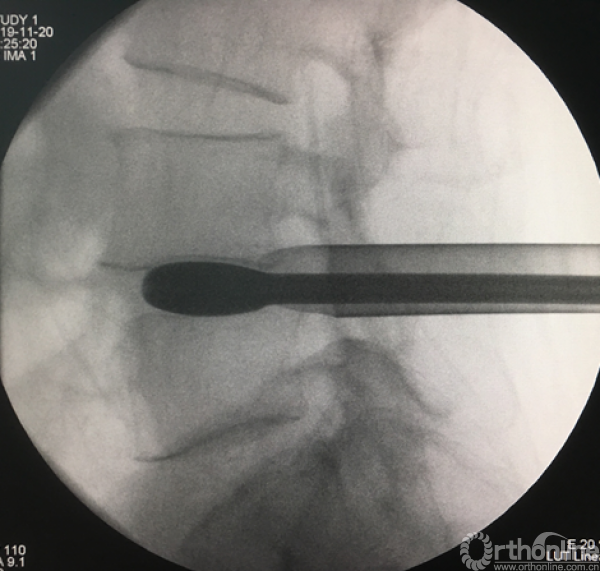

植入试模判断融合器大小

正侧位透视观察滑脱是否复位、融合器及植骨的位置